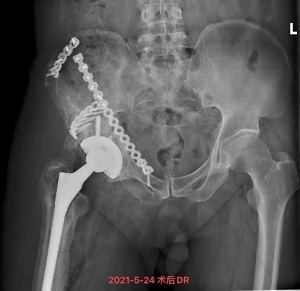

5月13日,饱受关节疼痛困扰的严爷爷在家人陪同下到我院就诊并入住关节骨病科。董克芳主任团队在仔细评估讨论后,制定了详细手术方案,并于5月21日为严嗲嗲进行了右人工髋关节翻修术,术后当日即指导其开始进行功能锻炼,1周后,严爷爷可下地行走,关节疼痛感也没了。28日,主管医生林少如反复叮嘱老人家一些注意事项后,严爷爷在家人陪同下出院回家了。

鉴于欧娭毑病情复杂,又年近八旬,且合并心肺等内科基础疾病较多,董克芳主任手术团队经讨论后,为欧娭毑制定了分期手术方案。1月26日,专家团队顺利为欧娭毑完成了右股骨内骨定取出术+右膝关节骨水泥旷置术。2月10日,大年三十前夕,欧娭毑顺利出院回家和家人一起过新年了。

3个月后,5月25日,按照既定手术方案,专家团队顺利为欧娭毑完成了人工全膝关节表面再置换术。目前,欧娭毑恢复良好,已在医师指导下进行下地负重及行走锻炼,医师查房时,欧娭毑忍不住感慨:“我这把年纪,实在是经不起折腾了,我来中医院住过很多回了,就相信你们中医院!”